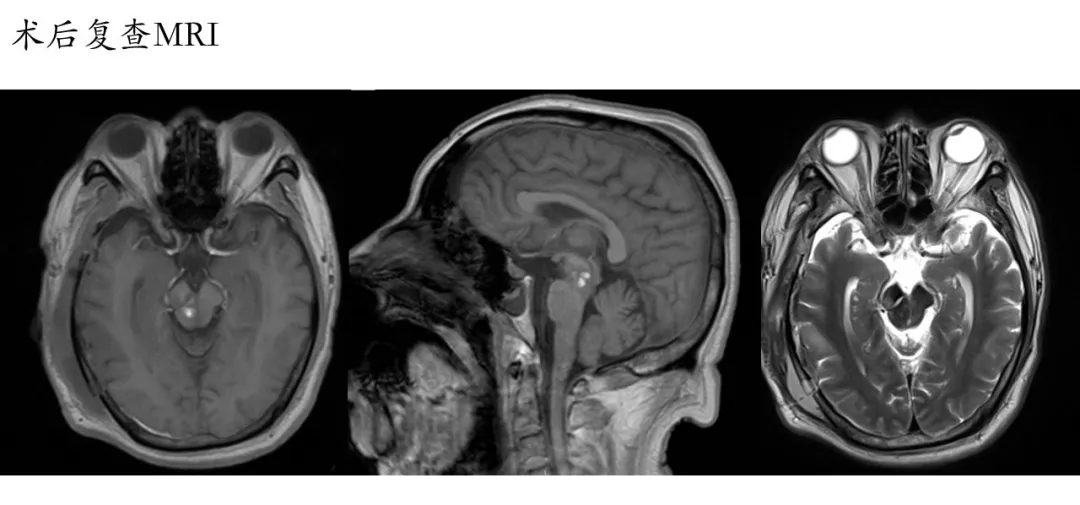

夹闭过程中,动脉瘤瘤颈撕裂,经多次尝试各种型号动脉瘤夹塑形均不满意。最后采用组合动脉瘤夹塑形+瘤颈破口棉片包裹方式夹闭动脉瘤(见链接视频),效果满意,颈内动脉通畅无狭窄,也无动脉瘤残留。术后病人恢复良好出院。